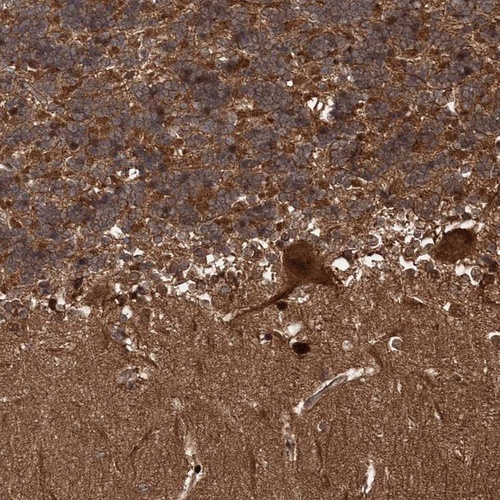

Immunohistochemical staining of human cerebellum shows strong cytoplasmic positivity in Purkinje cells, cells in molecular layer and in granular layer.